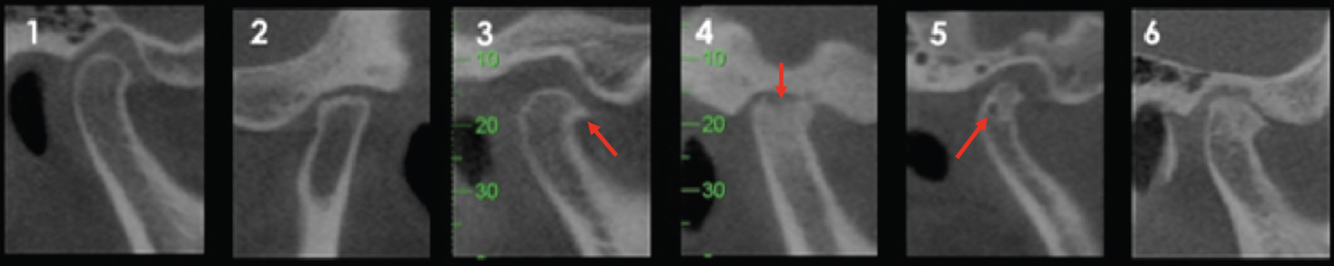

Q

TMJ Degenerative Changes: Label